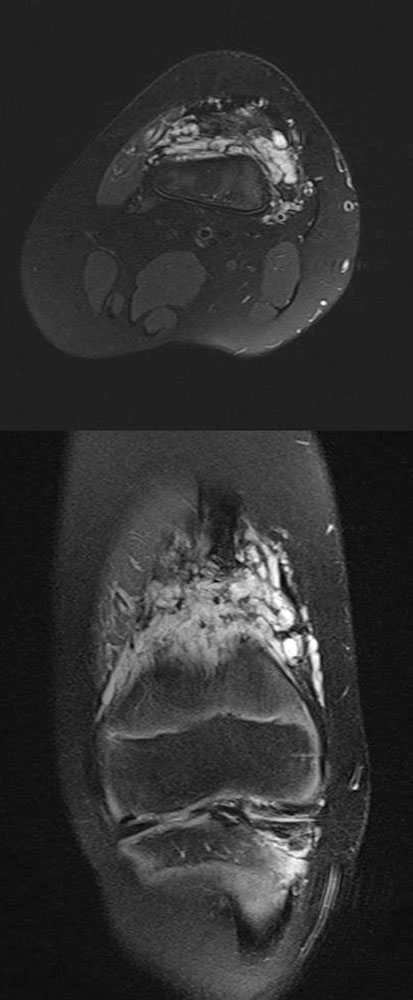

Folgeschäden treten am betroffenen Körperabschnitt dann auf, wenn infolge der Ausdehnung der venösen Malformation (VM) die Entwicklung benachbarter Strukturen wie Knochen, Gelenke, Muskeln und Sehnen gestört ist. Es ist anzunehmen, dass sowohl Verdrängung, gestörte Mikrozirkulation (herabgesetzte Oxygenierung bei Kongestion) als auch verminderter Gebrauch dabei eine Rolle spielen. Begleitend können zudem segmentale Überwuchs- und Minderwuchssyndrome auftreten, die nach neueren Erkenntnissen auf somatische Mutationen zurückzuführen sind. Diese Fälle zeichnen sich durch eine verstärkte Asymmetrie aus.

Die lokal entstehende muskuloskelettale Funktionsstörung wird zudem durch die zur kontralateralen Seite bestehende Asymmetrie weiter verschlimmert. Das Wachstum ist beeinträchtigt, was zu Schiefständen des Gesichtsschädels, der Wirbelsäule und der Extremitäten führen kann. Große venöse Malformationen im Gesicht können die Nahrungsaufnahme, das Gehör, die Sprache oder den Visus stören, sodass eine Therapie früh einsetzen sollte, um psychomotorische Entwicklungsverzögerungen zu vermeiden. Ausgedehnte venöse Malformationen an Unterarm- und Handmuskeln sind schmerzhaft und beeinträchtigen die Fingerbeweglichkeit. Das Kleinkind ist in seiner Wahrnehmung gestört. Greifen, Klettern und Schreiben werden, je nach dominanter Hand, nicht oder nur schlecht ausgeübt werden können. Diese Funktionseinbußen gilt es frühzeitig zu erkennen und anzugehen. Große venöse Malformationen am Bein können das Gehen und Rennen behindern, wodurch das Kind von Schulkameraden und Freunden isoliert werden kann.